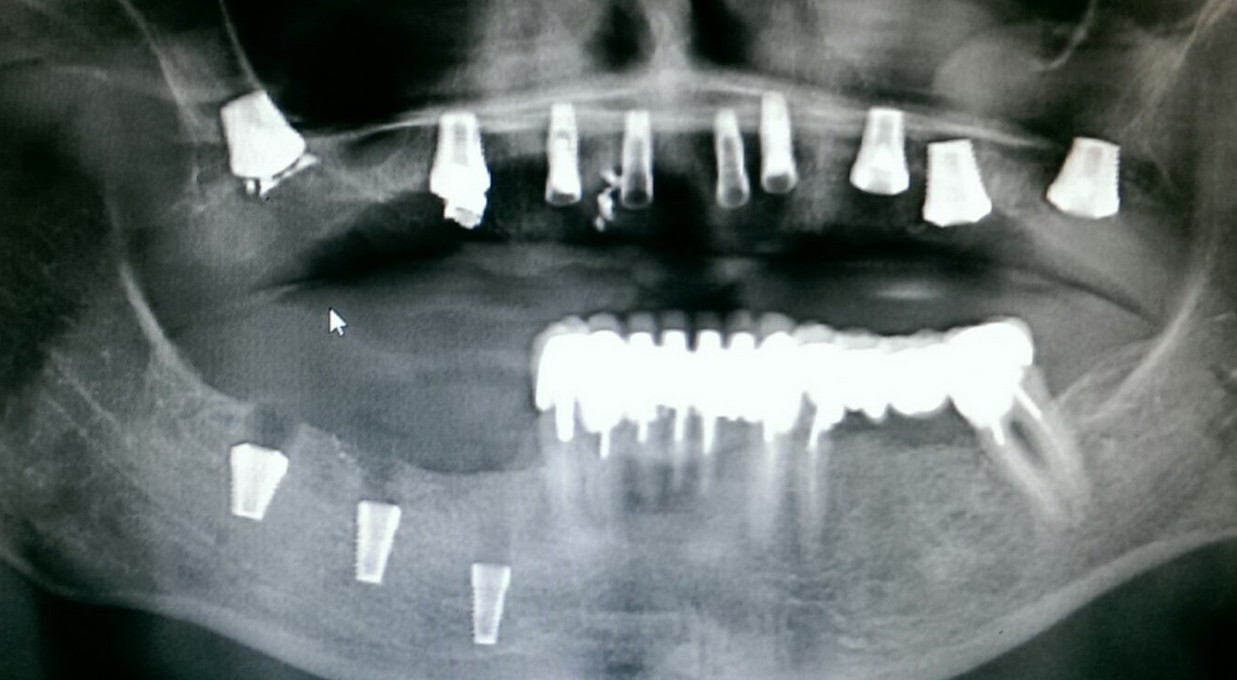

Случается чаще, чем можно представить. В основном, из-за убеждения ряда моих коллег в том, что конечная цель имплантологического лечения — это интегрированные импланты, а не протезирование на этих самых имплантах. Итог — ну вот, всё прижилось, пациент приходит к ортопеду, а тот разводит руками — типа, ничего не могу сделать. С одной стороны, ортопеда можно понять — на кривом фундаменте хороший дом не построишь. С другой стороны, некоторые имплантологи считают, что ортопеды просто неженки и лентяи, которым только подавай идеальные случаи. Особенно в создании данной проблемы отличаются некоторые челюстно-лицевые хирурги, не имеющие стоматологического образования:

То есть, хороший имплантолог мыслит больше как ортопед, а не как мясник челюстно-лицевой хирург.